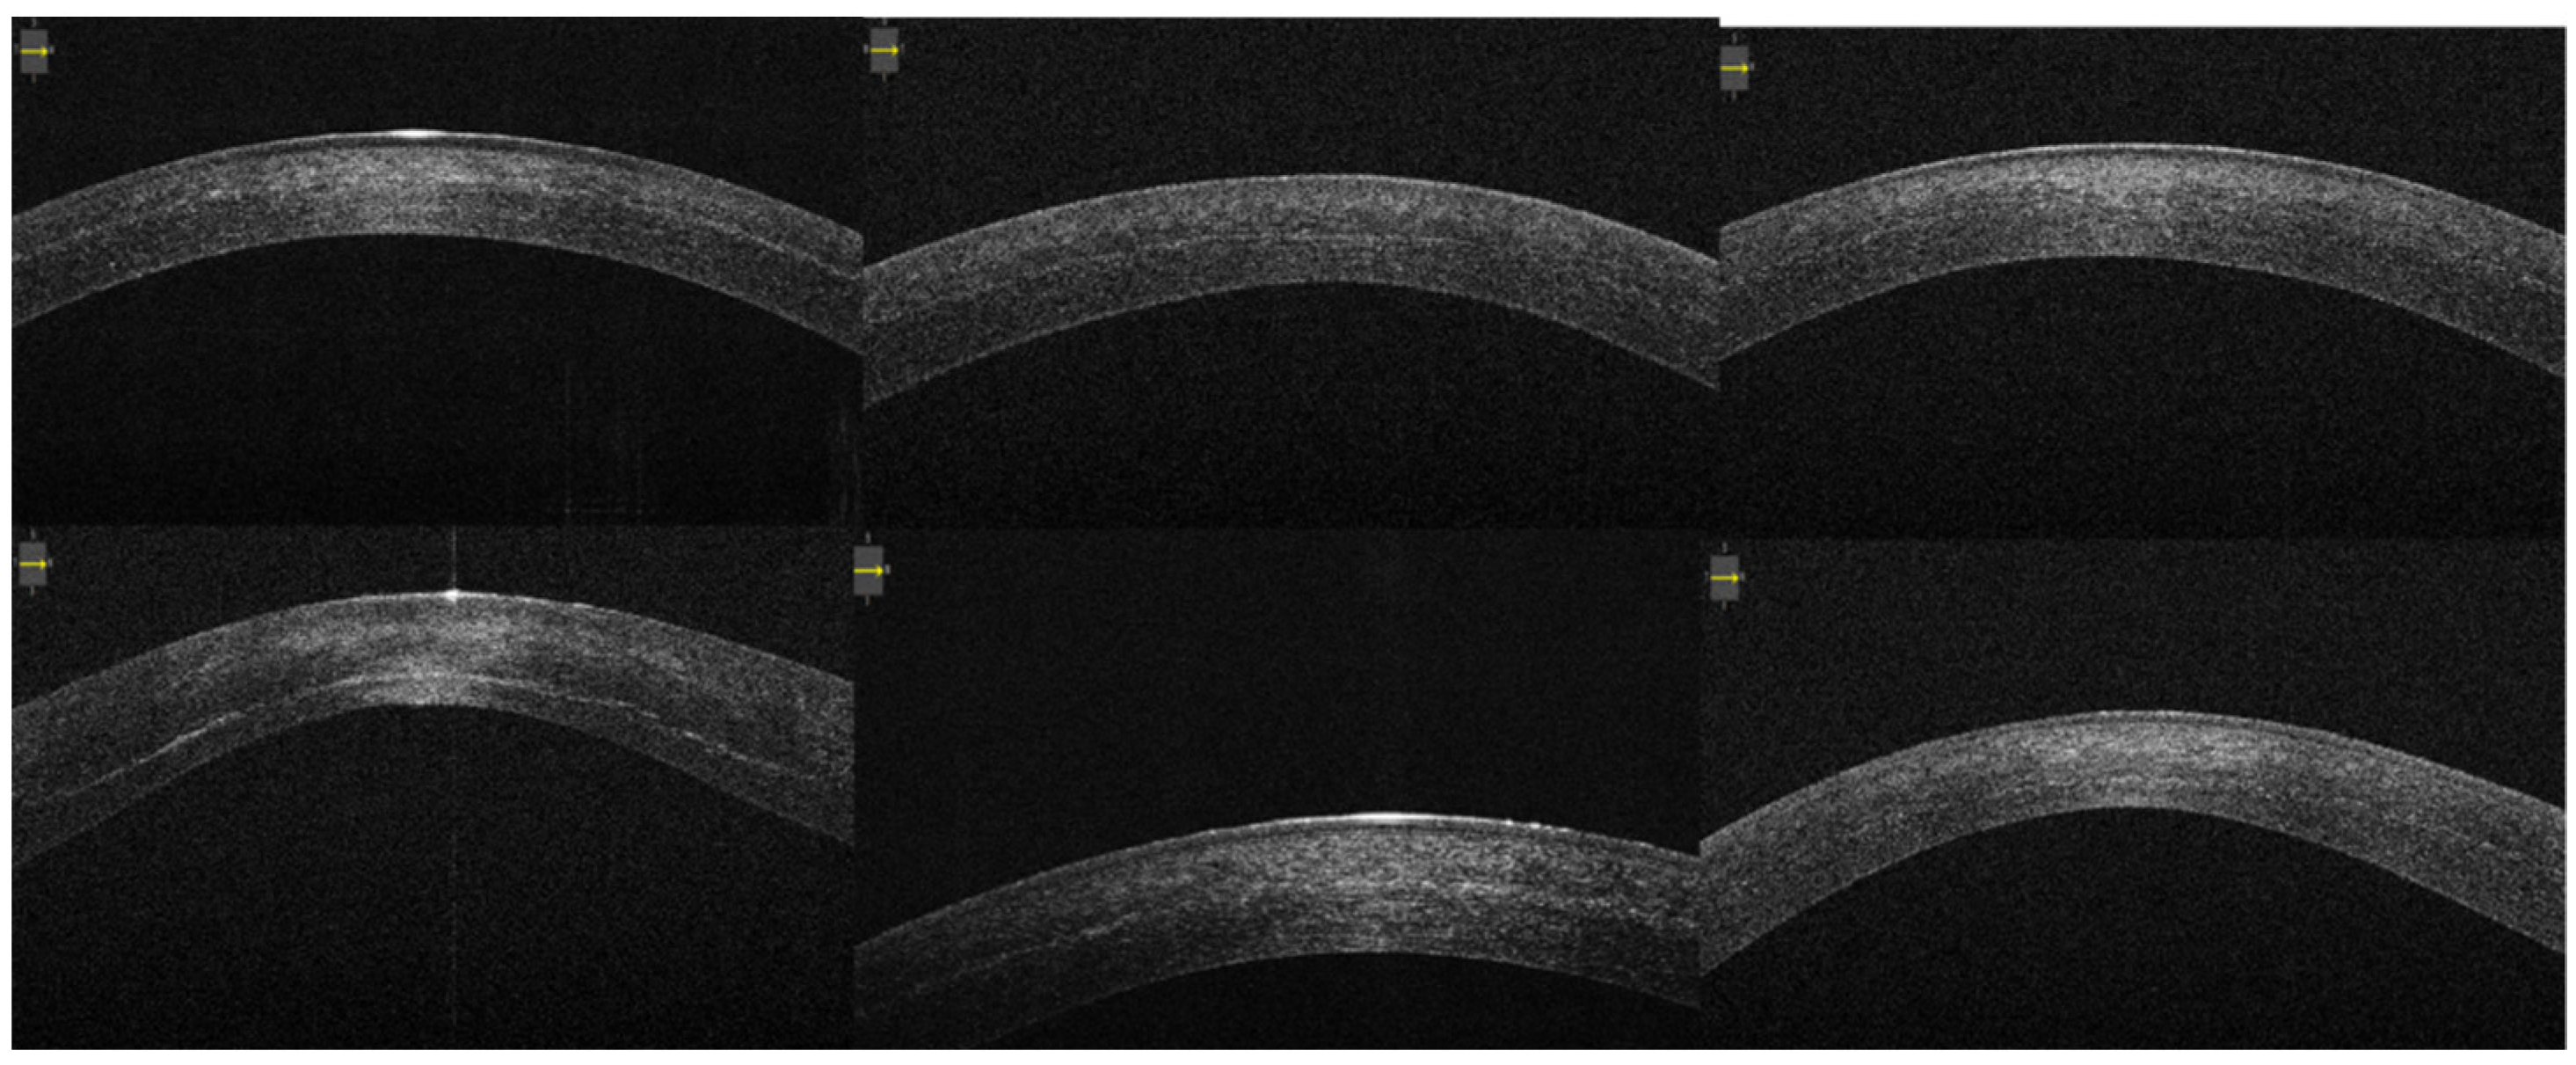

3. Results